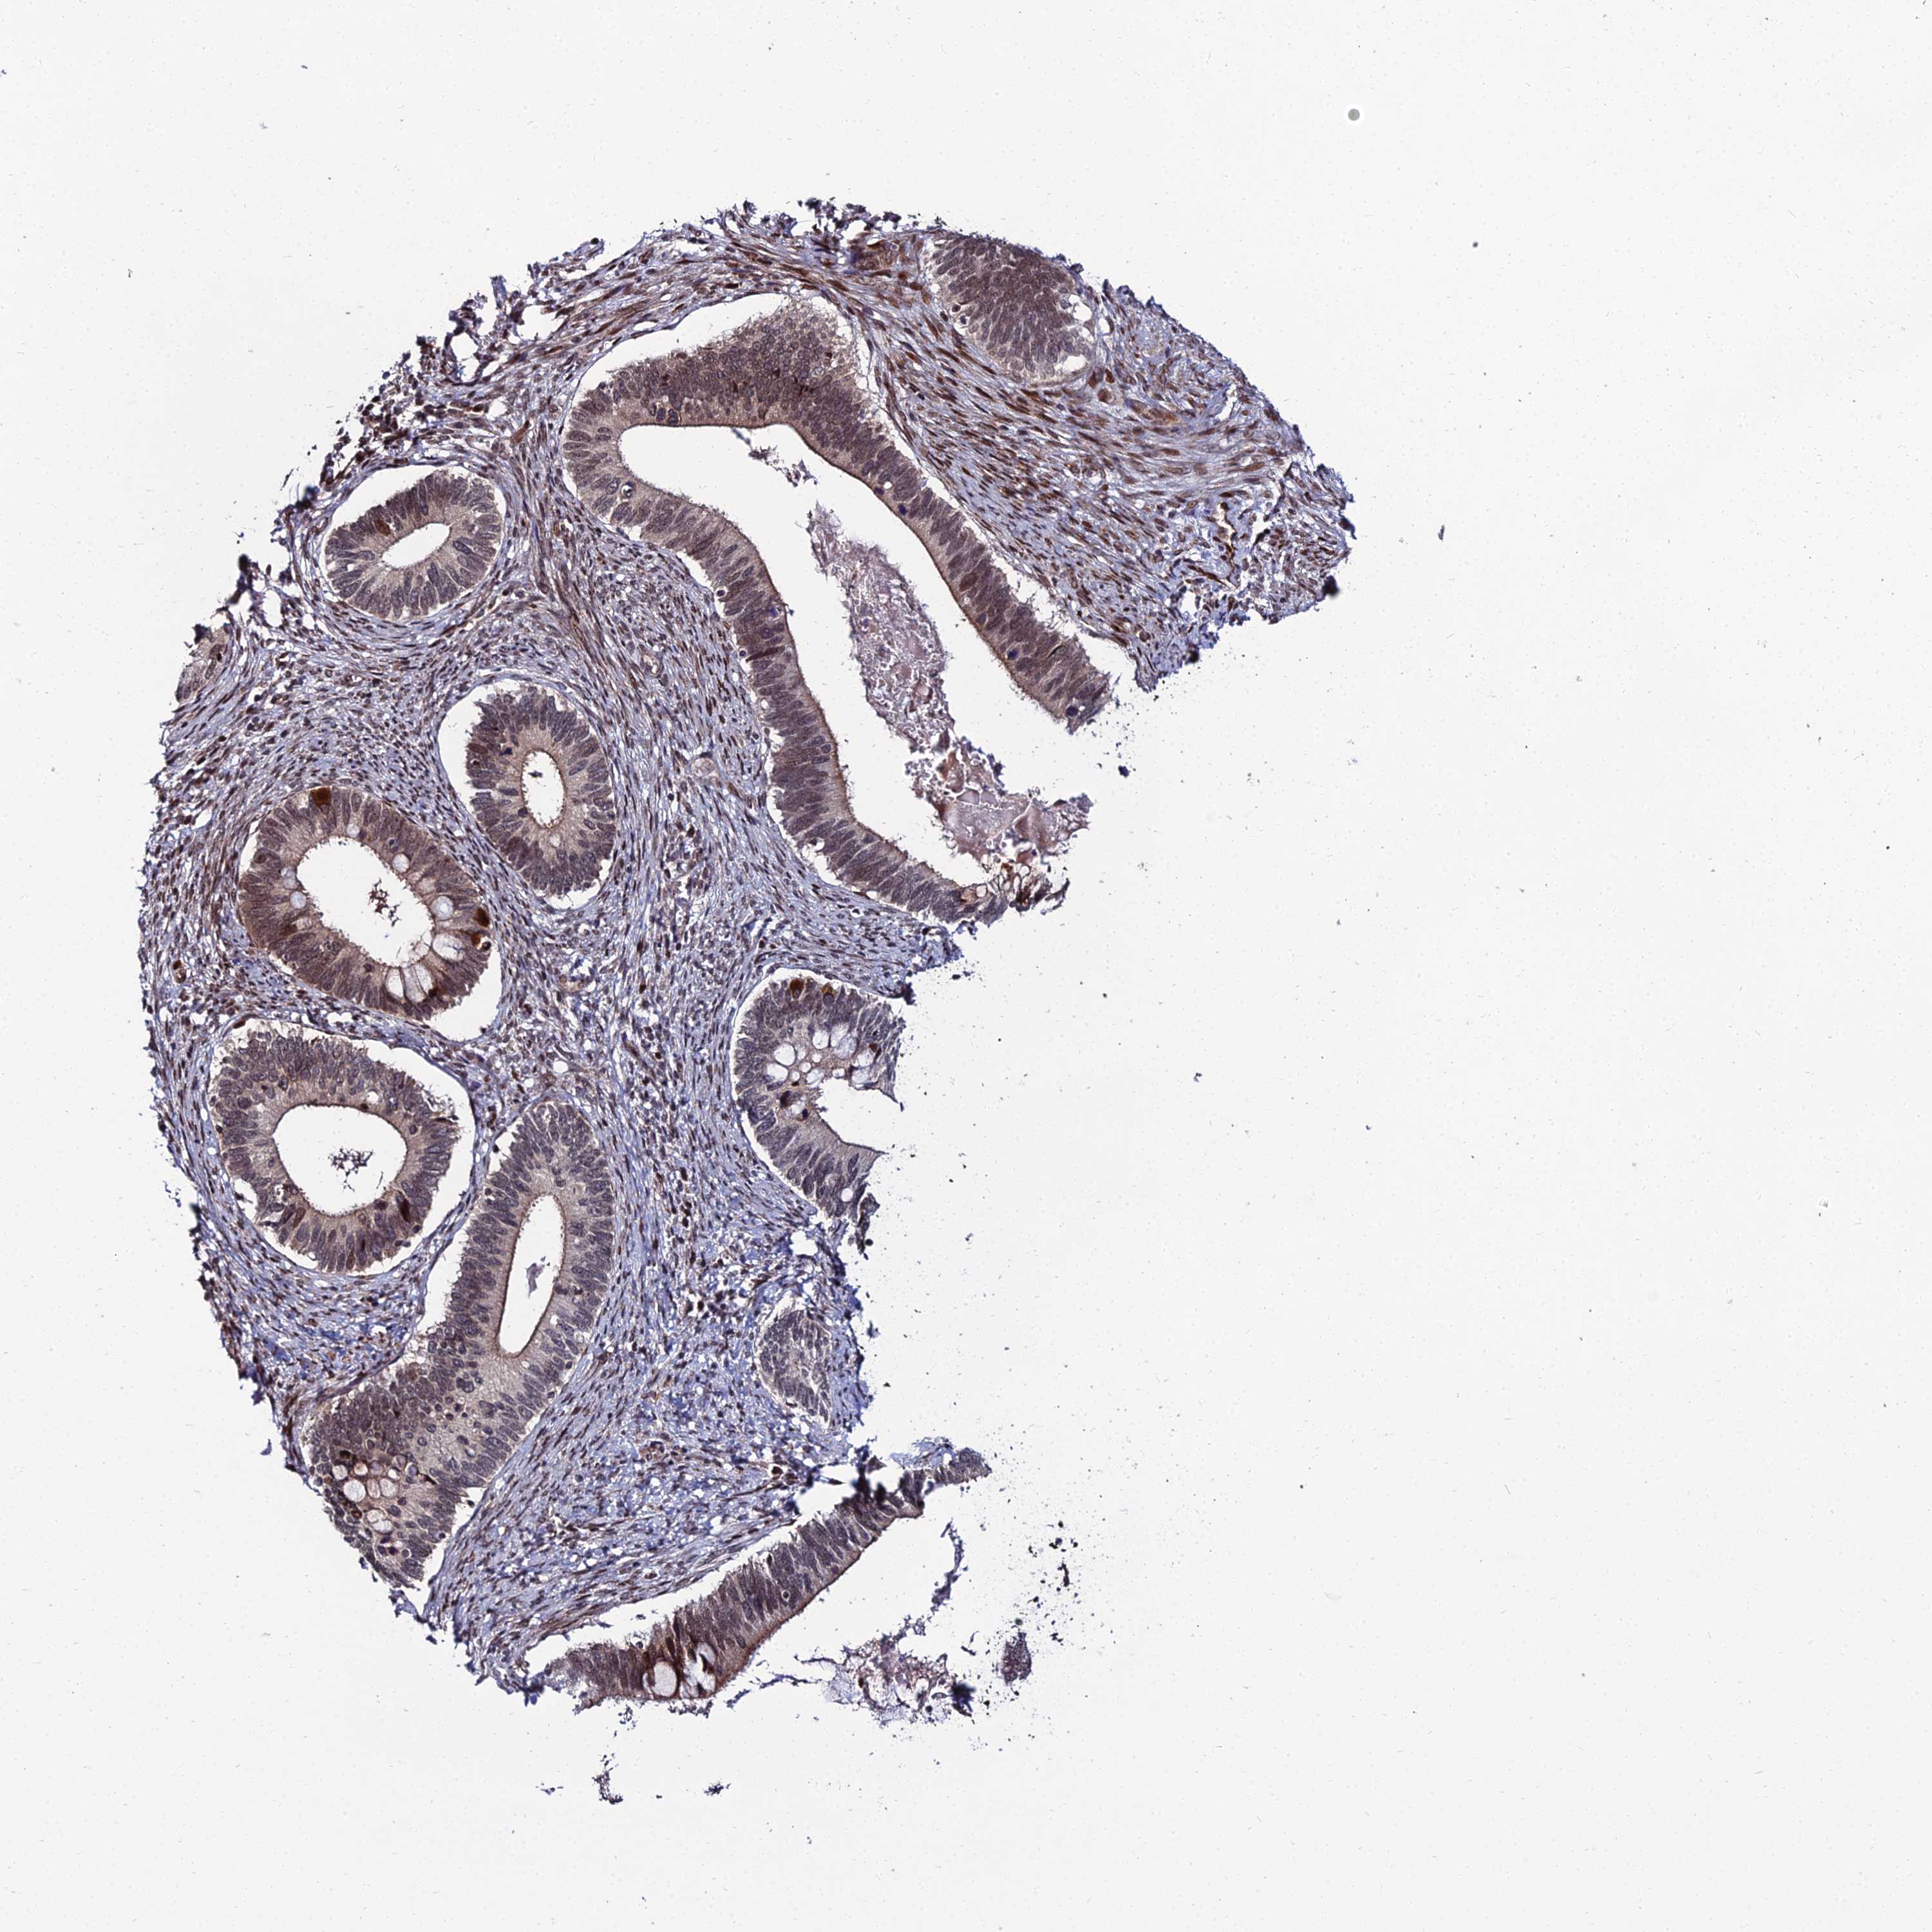

CERVICAL CANCER - Protein expressioni

A mouse-over function shows sample information and annotation data. Click on an image to view it in a full screen mode. Samples can be filtered based on level of antibody staining by selecting one or several of the following categories: high, medium, low and not detected. The assay and annotation is described here.

Note that samples used for immunohistochemistry by the Human Protein Atlas do not correspond to samples in the TCGA dataset.

Antibody stainingi

Antibody staining in the annotated cell types in the current human tissue is reported as not detected, low, medium, or high, based on conventional immunohistochemistry profiling in selected tissues. This score is based on the combination of the staining intensity and fraction of stained cells.

Each image is clickable and will lead to virtual microscopy that enables deeper exploration of all samples and also displays staining intensity scores, fraction scores and subcellular localization as well as patient and tissue information for each sample.

Antibody HPA043048

Staining

High

Medium

Low

Not detected

Intensity

Strong

Moderate

Weak

Negative

Quantity

>75%

75%-25%

<25%

None

Location

Nuclear

Cytoplasmic/membranous

Cytoplasmic/membranous,nuclear

Squamous cell carcinoma, NOS

Adenocarcinoma, NOS